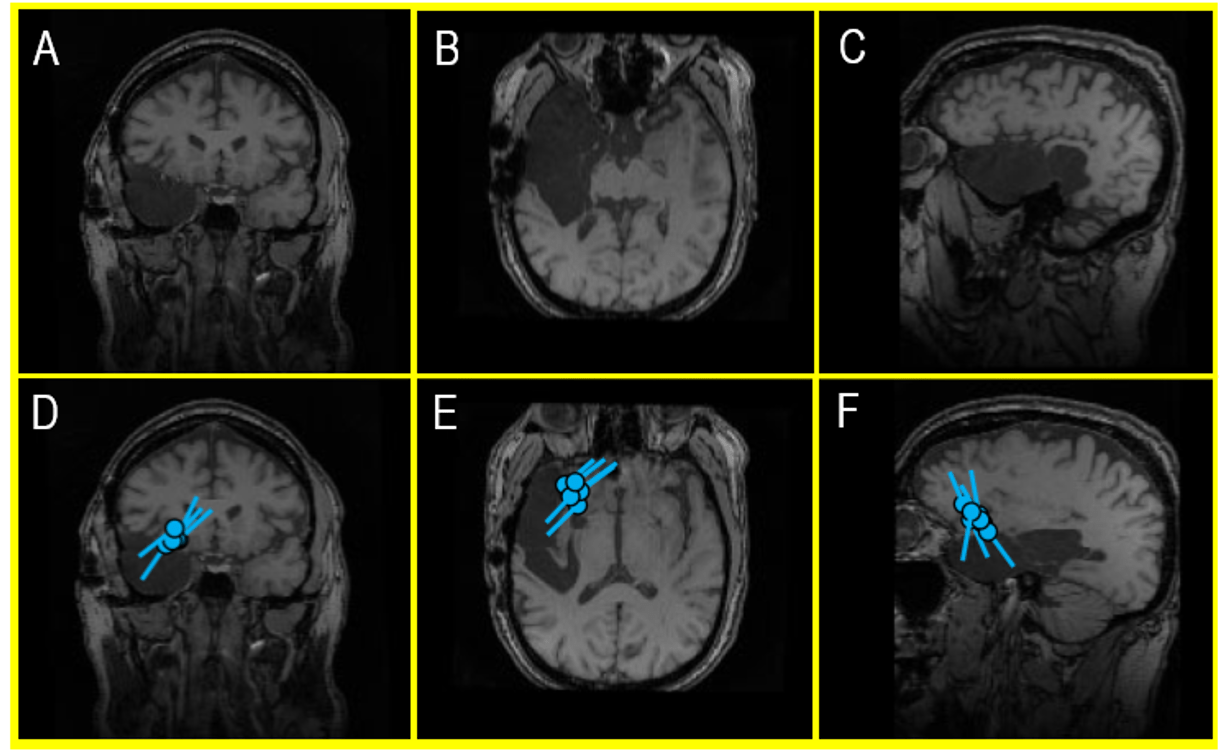

Figure 5 (A-F). An MRI of a recent external MEG referral patient (A, B, C) showing a large cavity following a right temporal lobectomy that ultimately failed to control the patient’s seizures with antiseizure medications (ASM). A second surgery was considered, but an EEG – in the context of a skull defect that distorts electrical signals – provided a misleading indication that the patient’s seizures continued to be produced in the remaining part of the right temporal lobe. However, a MEG – which is unaffected by surgically changed anatomy of the brain and skull – identified a very localized seizure focus within the inferior frontal gyrus (D, E, F). This area became the new center of attention and landmark for planning an invasive EEG monitoring prior to a new, targeted surgical intervention. During the clinical care of epilepsy patients, this kind of nonredundant information is invaluable for developing a treatment plan and the surgical outcomes.